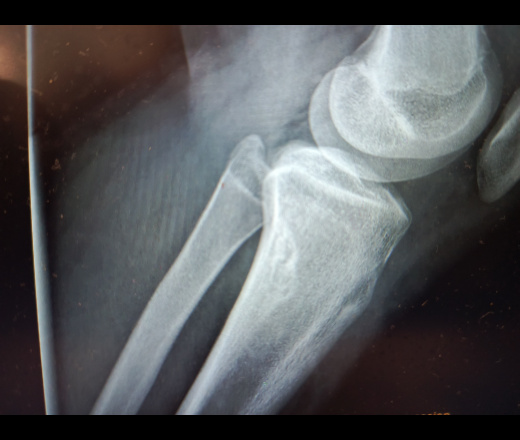

Пол пациента: Женский пол Тип патологии: ИнфекцияДоброкачественное новообразование, киста Область исследования: Скелетно-мышечная система Методы исследования: Rg Ребенок 16 лет, девочка. Боли в коленных суставах. Коллеги как можно дифференцировать данный дефект костной ткани ? Рг коленного сустава Рг коленного сустава Рг коленного сустава ID:94138 Цель публикации: Консультация Пт, 21/11/2025 - 16:47 #1 сергеев николай Не на сайте Был на сайте: 2 месяцев 1 неделя назад Зарегистрирован: 22.06.2016 - 18:45 Публикации: 4598 Написал абсцесс Броди, но берут сомнения Будьте осторожны со своими мыслями они начало поступков. Пт, 21/11/2025 - 19:01 #2 NIL Не на сайте Был на сайте: 6 дней 7 часов назад Зарегистрирован: 25.11.2013 - 20:50 Публикации: 18218 Я бы писала NOF "Слушай всех, прислушивайся к немногим, решай сам".© Пт, 21/11/2025 - 19:45 #3 сергеев николай Не на сайте Был на сайте: 2 месяцев 1 неделя назад Зарегистрирован: 22.06.2016 - 18:45 Публикации: 4598 NIL wrote: Я бы писала NOF Здравствуйте Наталия Ивановна! Вы бы написали NOF без диф.ряда с уверенностью? Будьте осторожны со своими мыслями они начало поступков. Пт, 21/11/2025 - 20:51 #4 Андрей Юрьевич Не на сайте Был на сайте: 1 неделя 10 часов назад Зарегистрирован: 16.11.2008 - 22:16 Публикации: 18106 сергеев николай wrote: NIL wrote: Я бы писала NOF Здравствуйте Наталия Ивановна! Вы бы написали NOF без диф.ряда с уверенностью? я бы тоже "без дифряда с уверенностью" Андрей Юрьевич Пт, 21/11/2025 - 21:38 #5 NIL Не на сайте Был на сайте: 6 дней 7 часов назад Зарегистрирован: 25.11.2013 - 20:50 Публикации: 18218 Андрей Юрьевич wrote: я бы тоже "без дифряда с уверенностью" +1 https://radiopaedia.org/articles/non-ossifying-fibroma-1 https://meduniver.com/Medical/luchevaia_diagnostika/rentgenogramma_mrt_fibroksantomi.html https://cyberleninka.ru/article/n/metafizarnye-fibroznye-defekty-i-neossifitsiruyuschiesy "Слушай всех, прислушивайся к немногим, решай сам".© Сб, 22/11/2025 - 07:58 #6 сергеев николай Не на сайте Был на сайте: 2 месяцев 1 неделя назад Зарегистрирован: 22.06.2016 - 18:45 Публикации: 4598 Большое спасибо! Будьте осторожны со своими мыслями они начало поступков.

Написал абсцесс Броди, но берут сомнения

Я бы писала NOF

Здравствуйте Наталия Ивановна! Вы бы написали NOF без диф.ряда с уверенностью?

я бы тоже "без дифряда с уверенностью"